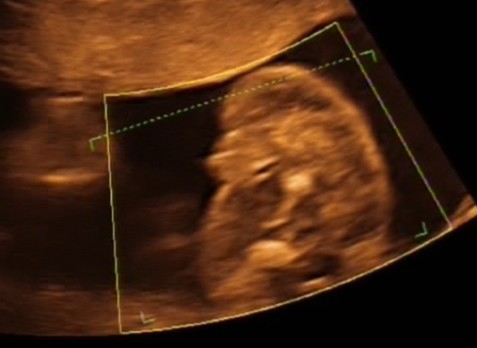

Więc pooglądałam sobie znów naszego szkraba, który dalej jest chłopakiem, czego w ogóle nie wstydzi się pokazywać.Widać siusiaka gołym okiem, więc mój synuś w dziewczynkę się na pewno nie zamieni.

Poza tym wystawiał na nas palec wskazujący, nie wiem czy groził nam czy co? Co dziwne ułożony już jak trzeba, główka na dole, a nogi to mam pod biustem, więc rozpycha się już nieźle. Kopie też mocno, więc ruchliwy i czy w tej pozycji wytrwa do końca? hmm... wątpię. Ale ogólnie dzidziuś zdrowy i wszystko ok. Moje łożysko na szczęście wyżej, ale nie aż tak i z tyłu więc dalej zakaz przytulanek i chyba to się już nie zmieni

Och jakaś taka szczęśliwa jestem, a nasz mały smyk nawet pokiwał nam rączką pokazując pięknie wszystkie paluszki. Chyba się zakochałam? A myślałam, że miłość będzie ciężko podzielić na dwóch. Ale teraz już wiem, że ona się nie dzieli tylko mnoży.....